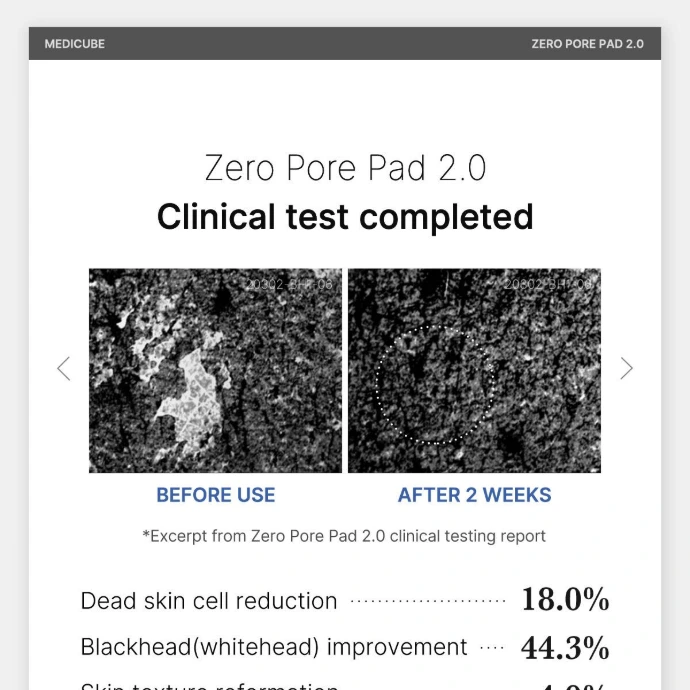

Idéal pour les peaux sujettes aux pores dilatés, à l’excès de sébum, aux points noirs, aux points blancs ou à une texture irrégulière, ce soin permet de réduire visiblement les pores, de limiter leur obstruction et d’améliorer l’hydratation de la peau. Les résultats sont prouvés : diminution du sébum jusqu’à 47,1 %, réduction des impuretés dans les pores jusqu’à 87,3 %, amélioration de l’hydratation et meilleure tenue du maquillage. Véritable best-seller de la K-Beauty avec plus de 400 millions d’unités vendues, ce produit est reconnu comme le pad resserre-pores numéro 1 de MEDICUBE.

- Résultats visibles rapidement (dès 2 semaines)